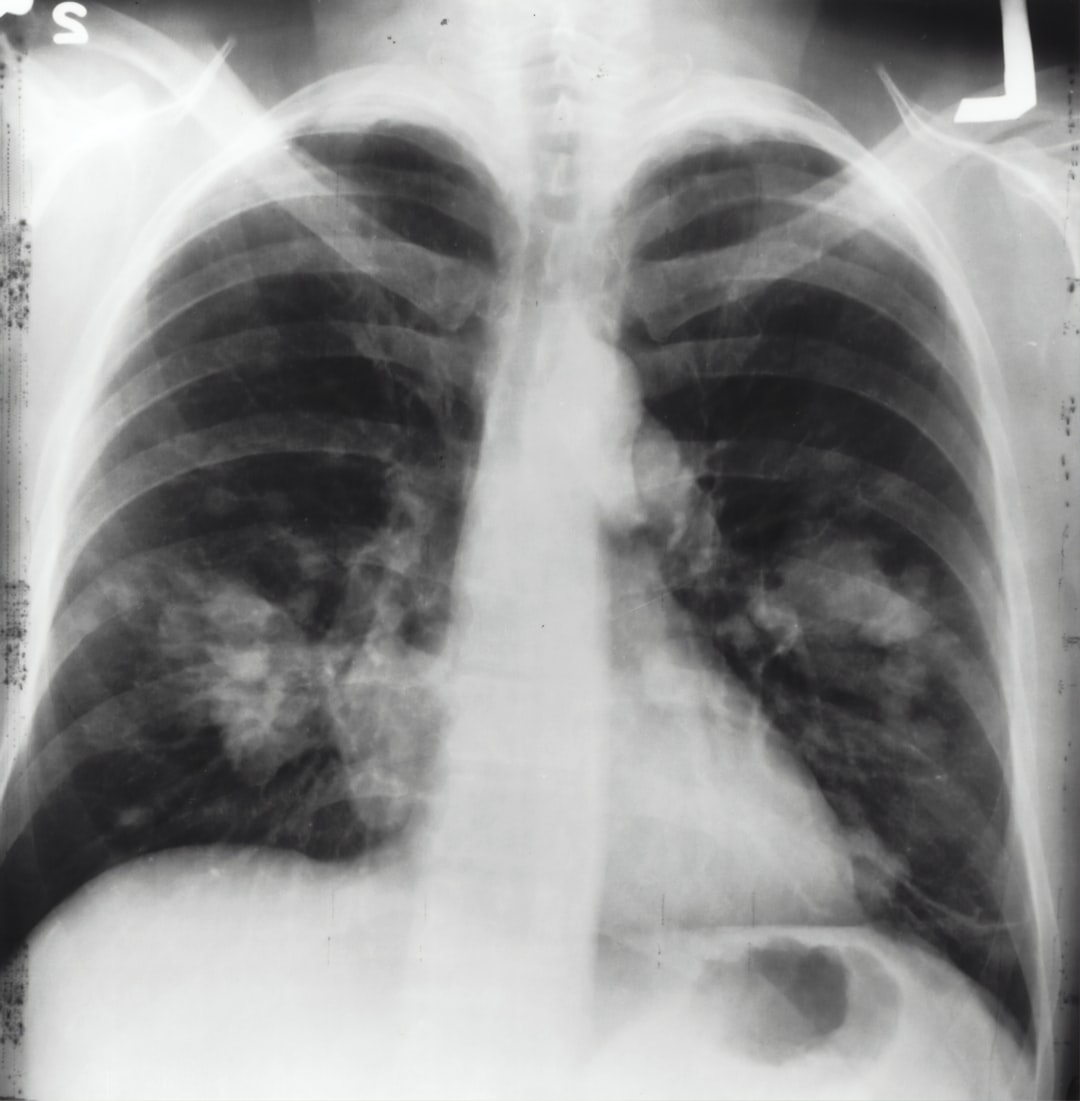

폐암은 전 세계적으로 가장 흔한 암 유형의 하나로, 그 심각성과 높은 발병률로 인해 많은 사람들에게 영향을 미치고 있습니다. 폐암은 폐에서 시작되는 악성 종양으로, 조기에 발견되지 않으면 치명적일 수 있습니다. 폐암은 흡연, 환경적인 요인, 유전적인 요소 등 다양한 원인에 의해 발생할 수 있으며, 주로 폐 조직에서 암세포의 비정상적인 성장과 전이가 일어납니다.

폐암은 초기 단계에서는 특별한 증상이 없을 수 있어 진단이 어려운 경우가 많습니다. 그러나 진행됨에 따라 기침, 호흡 곤란, 가슴 통증 등의 증상이 나타날 수 있으며, 이러한 증상은 환자와 주변 사람들에게 큰 고통을 안겨줍니다.